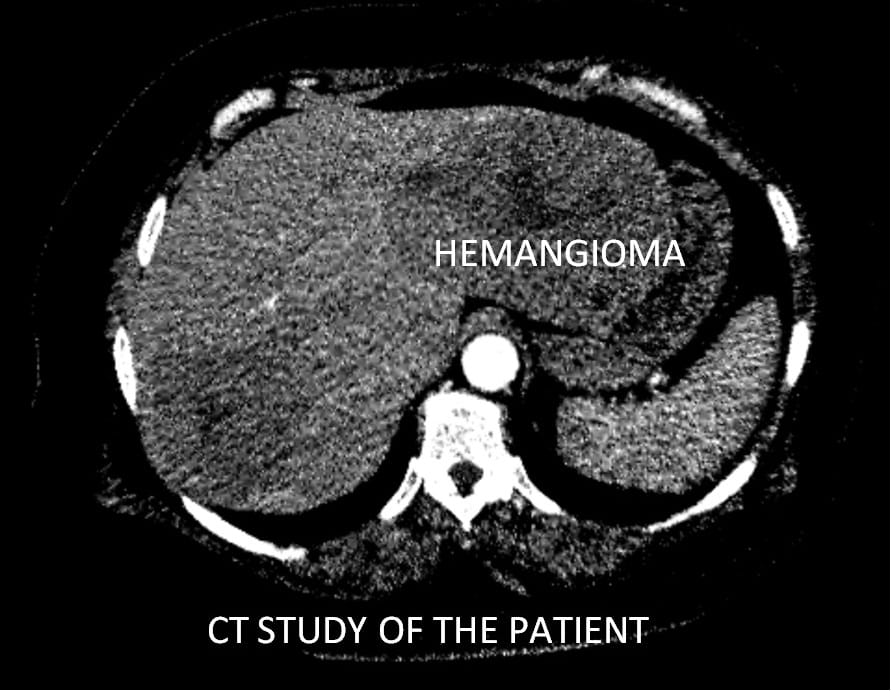

قام اليوم الفريق الطبى بقسم الأشعة التداخلية بمستشفيات جامعة بنها وبمساعدة لواء طبيب اسامه زين أستاذ الاشعة التداخليه بالاكاديمية الطبية العسكرية بإجراء عملية حقن ورم كبدي كبير الحجم لمريضة تبلغ من العمر 51 عاما وذلك بعد عمل اشعة مقطعية ورنين مغناطيسي لتحديد طبيعة الورم.

حيث تعد هذه العملية الاولى من نوعها التى يتم عملها من خلال جهاز الأشعة المقطعية ١٢٨ متعدد المقاطع حيث تم علاج الورم من خلال قسطرة بالشريان الكبدي للفص الأيسر من الكبد ونجاح عملية الحقن التي تظهر اختفاء الاوعيه الدمويه المغذيه للورم.